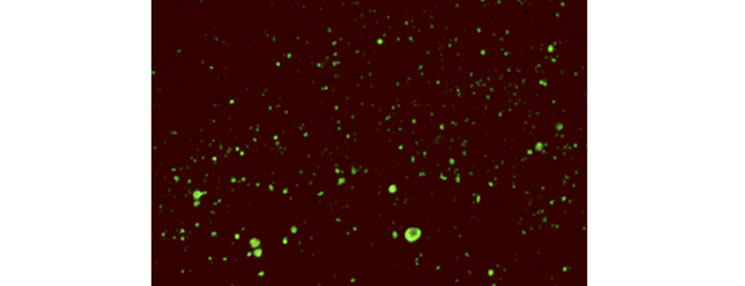

Odnos u veličini mužjaka i ženke T. spiralis

| Izdvojena ličinka

| Ličinka u mesu unutar čahure |